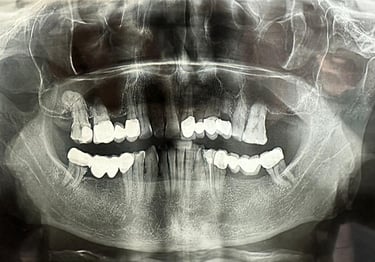

Se deceleaza imagistic o formatiune tumorala radiotransparenta, de mari dimensiuni, localizata la nivelul intregului grup frontal mandibular.

Dupa examenul clinic si imagistic se pune diagnosticul prezumtiv de formatiune tumorala chistica (chist radicular de mari dimensiuni). Se intervine chirurgical realizandu-se extractiile dintilor cauzali, irecuperabili, rezectii apicale a dintilor implicati chistic, care au fost tratati endodontic in prealabil. Piesa operatorie a fost trimisa catre examenul histopatologic, diagnosticul fiind chist radicular fara atipii.